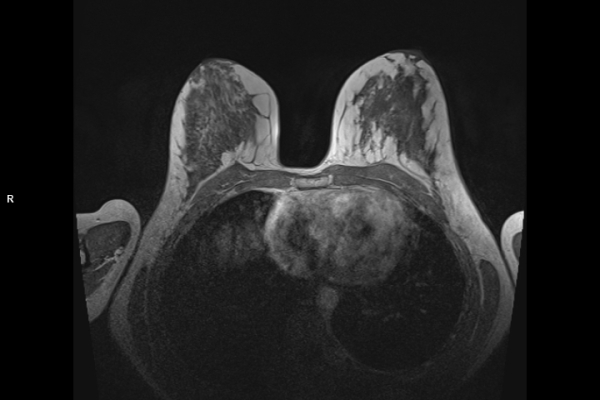

Detailbild MRT

Die MRT (Magnetresonanztomographie) arbeitet mit Magnetfeldern und Radiowellen und eignet sich besonders für Untersuchungen der Weichteile wie Gehirn, Muskeln oder Gelenke. Die CT (Computertomographie) nutzt Röntgenstrahlen und liefert schnelle, hochauflösende Bilder, insbesondere für Knochen, Lunge oder innere Organe. Die Wahl der jeweiligen Untersuchung richtet sich an das individuelle Krankheitsbild und wird bei der Überweisung festgelegt.

Wir bieten ein breites Spektrum an Untersuchungen an, von Standarduntersuchungen der Gelenke, Organe oder großflächigen Körperregionen bis zu Spezialuntersuchungen zum Beispiel des Herzen oder der Gefäße. Zusätzlich werden Angiographien (Darstellung von Blutgefäßen), Endometriose-Abklärungen und Mamma-Untersuchungen durchgeführt. Genauere Details können Sie der MRT/CT-Übersicht und der Preisliste entnehmen, oder Sie wenden sich direkt an unser Team, das Sie gerne zur passenden Untersuchung berät.